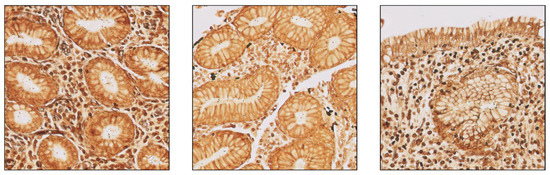

3.1. The Algorithm Can Automatically Detect H. Pylori on Gastric Samples